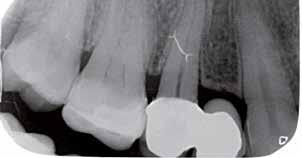

A fogszabályzó kezelések egyik legfontosabb célja, hogy elérjük a lehető legharmonikusabb interokkluzális fogérintkezéseket, továbbá az állcsont relációs helyzetének frontális és szaggitális síkban is megfelelőnek kell lennie. A fogszabályzás befejezésekor a fogpozícióknak nem orthodonciai, hanem protetikai szempontok szerint kell ideálisnak lenniük. Az Invisalign ClinCheck szoftver (Align Technology) segítségével a protetikus az orthodontussal együtt meg tudja határozni azokat a végső fogpozíciókat, amelyek a lehető legjobb végeredmény biztosításához elengedhetetlenek. Bizonyos klinikai paramétereket, mint a fogak klinikai koronájának nagyságát, az egyes fogak fogíven belüli optimális pozícióját, a fogívek egymáshoz viszonyított helyzetét, a fogak között látható rések nagyságát, a frontfogak tengelyének dőlését, az overjet és overbite mértékét már a kezelések megkezdése előtt pontosan definiálni kell. Ezeket az adatokat viszont csak a tervezett végleges fogpótlás ismeretében lehet meghatározni, ezért van szükség az orthodontus és a protetikus szoros együttműködésére.